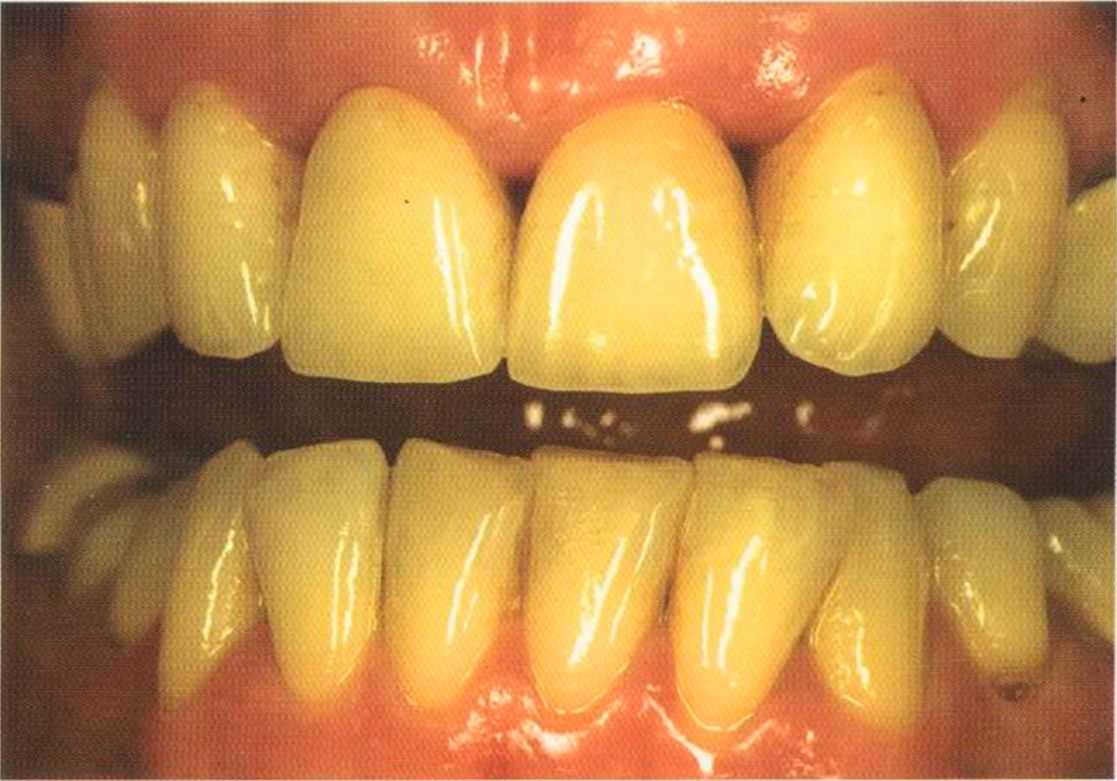

Результат с использованием In-Ceram развеял все сомнения, и решение об изготовлении коронки на другой боковой резец не заставило себя долго ждать.

После того как мы определит цвет зуба, решено быо сначсьа изготовить одну коронку.